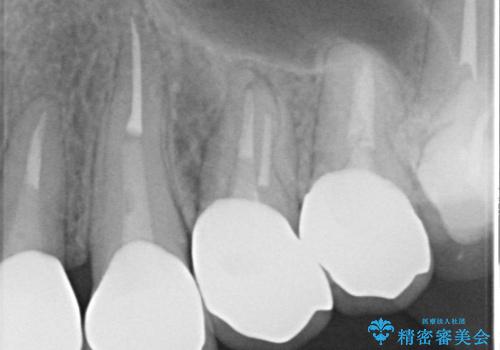

- 全体的な治療と、見た目をきれいにしたとのご希望で来院されました。

上顎の前歯はガタガタがあり、過去に治療した歯はつぎはぎのようになっており、審美的に周囲と調和がとれていない状態でした。

治療計画としては

①仮歯を装着

②矯正治療

③セラミック装着

の順で行いました。